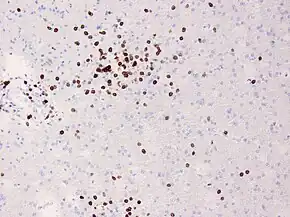

In Rasmussen's encephalitis, there is chronic inflammation of the brain, with infiltration of T lymphocytes into the brain tissue. In most cases, this affects only one cerebral hemisphere, either the left or the right. This inflammation causes permanent damage to the cells of the brain, leading to atrophy of the hemisphere; the epilepsy that this causes may itself contribute to the brain damage. The epilepsy might derive from a disturbed GABA release,[7] the main inhibitory neurotransmitter of the mammalian brain.